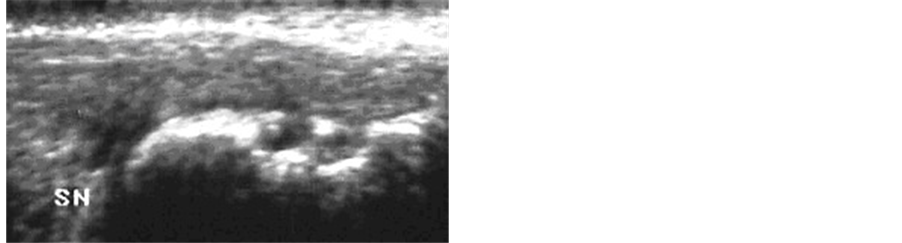

For all subjects of the group A, the echography at T0 demonstrated the presence of an area of hypoechogenicity in the mid portion of the Achilles tendon with an increase of the microvascularity (Figure 1). In group B subjects an absence of alteration in the echographic characteristics of the tendon was demonstrated (Figure 2).

Figure 1. Group A, before treatment: diffuse hypoechogenicity areas (arrows) and thickening of the tendon with intense paratendon microvascularity.